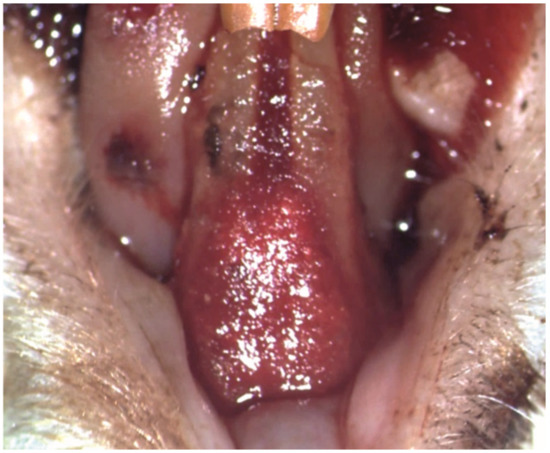

After the induction of periodontitis, during phase 2, the gingival epithelium exhibited zones of necrosis and ulceration, associated with a dense chronic inflammatory infiltrate in the underlying lamina propria (Figure 10A). The periodontal ligament contained extensive zones of chronic inflammation, with edema, dilated blood vessels, and inflammatory infiltrate with polymorphonuclears, lymphocytes and macrophages; the fiber groups were detached from the alveolar bone (Figure 10B). The alveolar bone was resorbed, with large areoles and thin trabeculae in the central spongiosa. The blood vessels in the pulp core were congested (Figure 10C).

Figure 10. Histological aspect after induction of periodontitis in Phase 2: (A) the gingiva with ulcerated epithelium and dense inflammatory infiltrate in the lamina propria; (B) rich chronic inflammatory infiltrate in the periodontal ligament; (C) resorption of the alveolar bone and detachment of the periodontal ligament; Goldner’s trichrome staining.